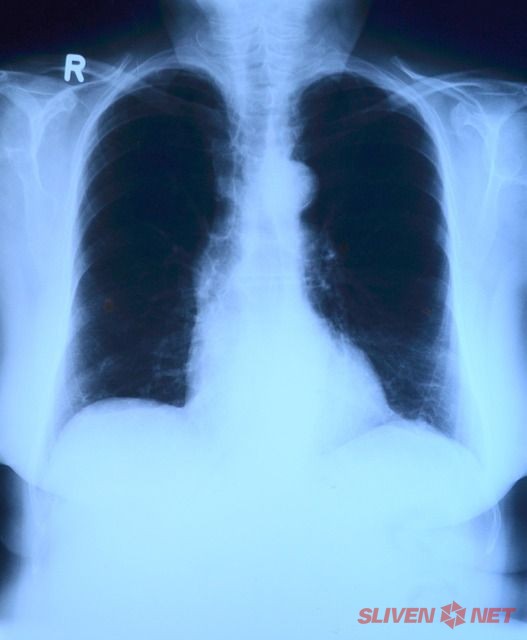

Безплатни прегледи за туберкулоза ще се извършват до 8 декември в специализирания кабинет в сектора по фтизиатрия към Многопрофилната болница за активно лечение (МБАЛ) "Д-р Иван Селимински"- Сливен, съобщиха от болничното заведение.

От 8:00 до 12:00 часа на всеки желаещ ще се проведе скрининг на риска за туберкулоза чрез анкета, консултации, прегледи и допълнителни изследвания на съмнителните за туберкулоза лица, като ще преглежда д-р Снежана Колева.

МБАЛ "Д-р Иван Селимински" провежда периодично безплатни прегледи за туберкулоза, като последният скрининг бе през септември, т.г. Заболеваемостта в област Сливен е над средната за страната.